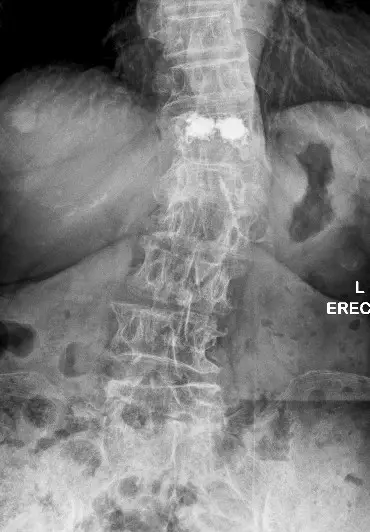

X‑rays and MRI revealed a T12 burst fracture, a serious osteoporotic injury, despite what seemed like a minor fall.

After discussing options, she chose vertebroplasty. Bone cement was injected into the fractured vertebra under imaging guidance. Risks—mainly cement leakage—were minimised through precise technique.